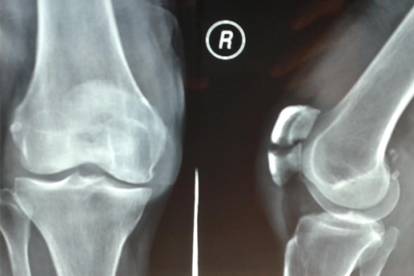

髌骨骨折后肌肉萎缩怎么回事

髌骨骨折后肌肉萎缩可能由长期制动、神经损伤、营养不良、血液循环障碍、炎症反应等原因引起,可通过康复训练、物理治疗、营养支持、药物治疗、手术治疗等方式改善。